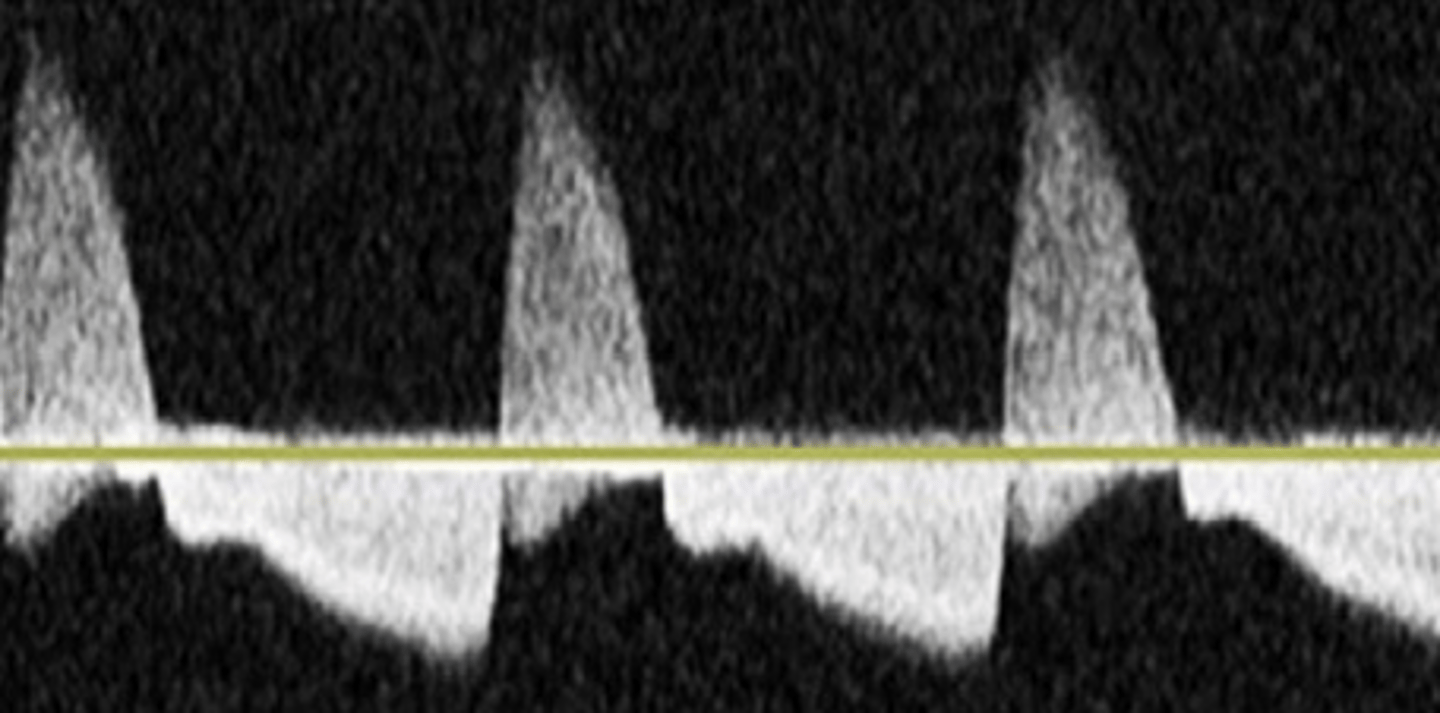

Intermediate Resistance

-sharp upstoke/brisk downstroke

-forward flow throughout

-end systolic notch